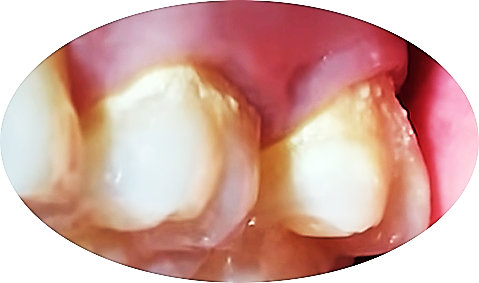

잇몸과 치아 경계에 치석이 생기면 염증이 생기기 쉽고 이로 인해 잇몸이 민감해져 혈관이 확장되어 통증과 출혈이 생길 수 있습니다.

대부분 마취하지 않고 초음파 기구로 치석제거를 하지만

염증이 심하고 치석이 잇몸 깊숙이 파고 들어가 있는 경우에는 초음파 기구와 수기구를 함께 사용해서 치석을 제거합니다.